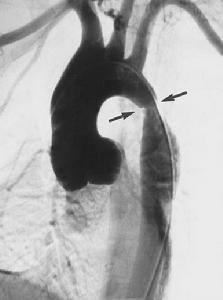

庫欣綜合徵 6、主動脈縮窄 多數為先天性血管畸形,少數為多發性大動脈炎所引起。特點為上肢血壓增高而下肢血壓布告或降低,呈甚至血壓高於下肢的反常現象。在肩胛間區、胸骨旁、腋部可有側支循環動脈的搏動和雜音或腹部聽診有血管雜音。胸部X線攝影可顯示肋骨受側支動脈侵蝕引起的切跡。

主動脈造影2、顱內蝶鞍X線檢查、腎上腺CT掃描及放射性碘化膽固醇腎上腺掃描可用於病變定位。

3、主動脈造影可確定診斷主動脈縮窄。